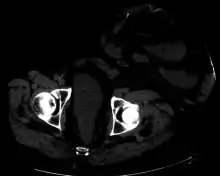

![]() مخطط يوضح فغر القولون | |